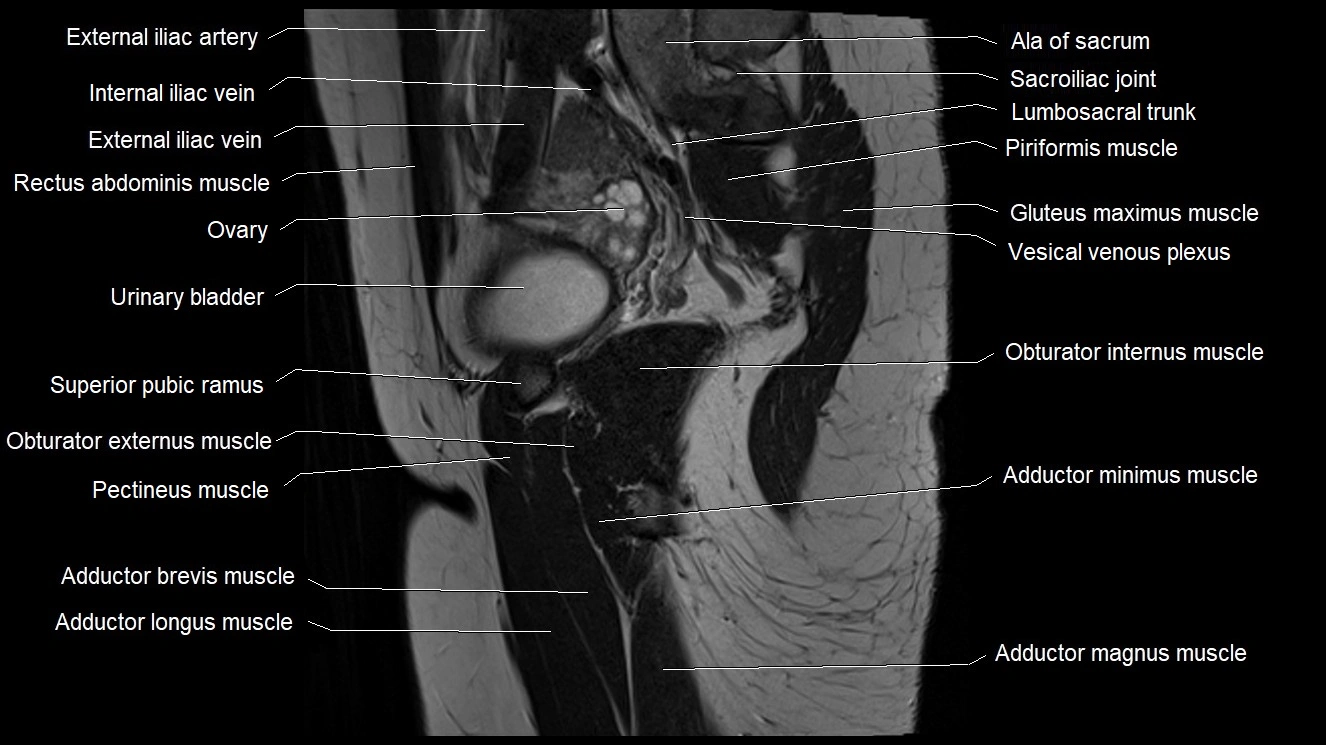

- Ala of sacrum

- External iliac artery

- External iliac vein

- Gluteus maximus muscle

- Lumbosacral trunk

- Obturator internus muscle

- Ovaries

- Pectineus muscle

- Sacroiliac joint

- Superior pubic ramus

- Urinary bladder